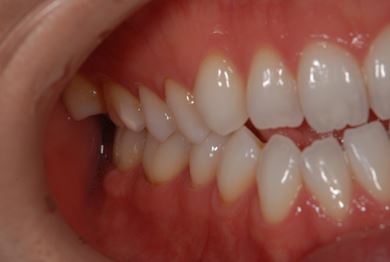

治療前

• 治療前